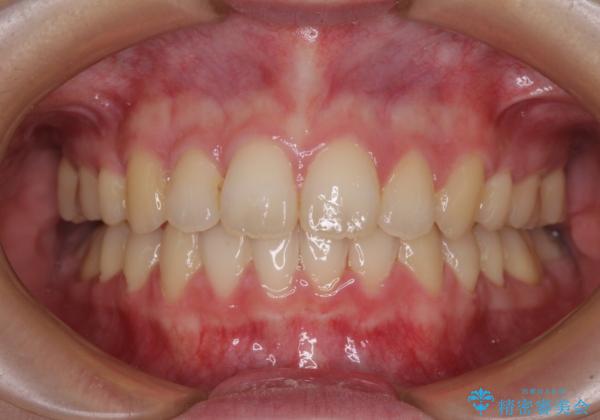

左側の咬み合わせと上下正中の位置をコントロールするために時間がかかりましたが、事前に思い描いた通りの歯列に整い、患者様には大変満足していただきました。